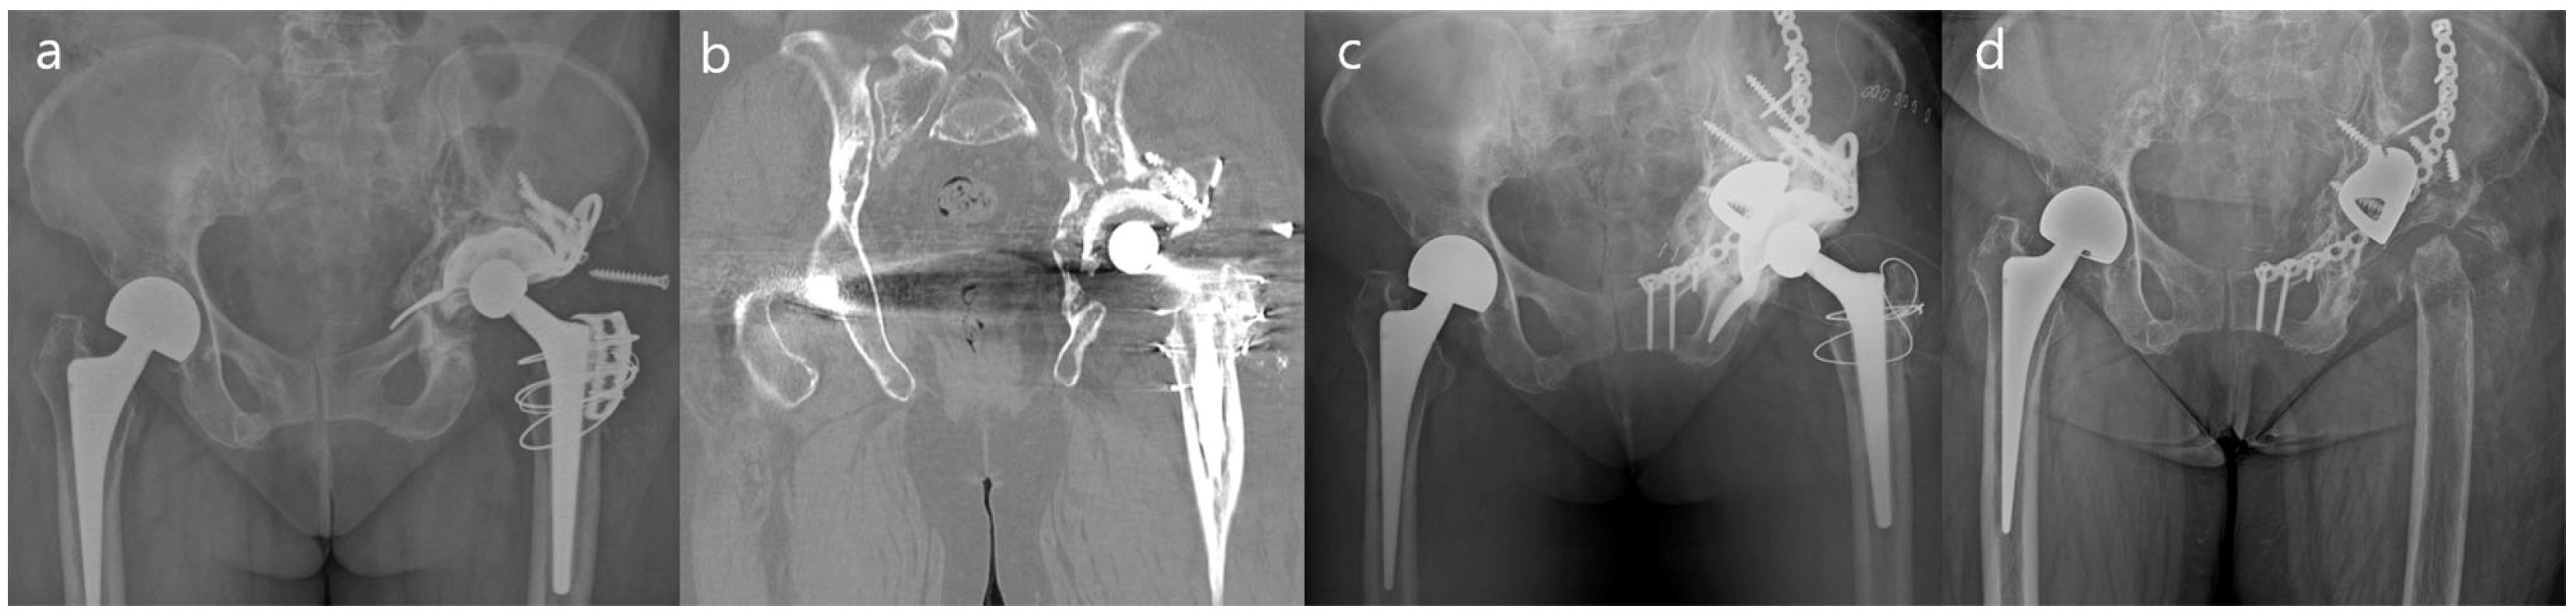

| Case | Sex/Age | BMI * (kg/m2) | BMD * (T-Score) | Reason for Index Surgery | Reason for Final Revision Surgery | No. of Revision Surgery | Follow-Up Duration (Months) |

|---|---|---|---|---|---|---|---|

| 1 | F/44 | 24.1 | −1.1 † | Traumatic OA | Cup loosening | 2 | 112.0 |

| 2 | M/71 | 21.6 | −3.3 | Femoral Neck Fx | All component loosening | 3 | 112.0 |

| 3 | F/69 | 34.1 | −2.1 | Traumatic OA | Cup loosening | 2 | 106.7 |

| 4 | M/65 | 28.1 | −2.6 | Femoral Neck Fx | All component loosening + ceramic liner Fx | 1 | 96.0 |

| 5 | M/58 | 26.3 | −1.0 | Traumatic ONFH | Acetabular destruction after monobloc arthroplasty | 1 | 112.0 |

| 6 | M/50 | 29.0 | 0.9 | Idiopathic ONFH | Cup loosening | 2 | 107.9 |

| 7 | M/75 | 21.7 | −1.9 | Traumatic ONFH | All component loosening + ceramic liner Fx | 3 | 100.0 |

| 8 | F/71 | 26.2 | −3.1 | Traumatic OA | Cup loosening | 4 | 101.1 |

| 9 | M/60 | 24.9 | −0.7 | Septic Hip Sequalae | Cup loosening | 1 | 99.6 |

| 10 | F/80 | 19.5 | −2.8 | LCP Sequalae | Cup loosening | 3 | 96.0 |

| Case | Side | Operation | Paprosky | Implants | Additional Procedure | Final HHS | Postop Cx |

| 1 | Lt | Total a | 3A | B-S + TM + Mesh | GTO + Grip plate | 85 | - |

| 2 | Lt | Total | 3A | B-S + TM | Trochanter wiring | 91 | - |

| 3 | Lt | Cup b | 3B | B-S + TM | - | 73 | PJI |

| 4 | Lt | Cup | 3B | B-S + TM | - | 72 | Acute D/L |

| 5 | Lt | Total | 3A | B-S + TM | ETO + Wiring | 86 | - |

| 6 | Lt | Cup | 3A | B-S + TM | GTO + Grip plate | 90 | - |

| 7 | Lt | Cup | 3A | B-S + TM | - | 81 | - |

| 8 | Lt | Cup | 3A | B-S + TM | GTO + Grip plate | 79 | - |

| 9 | Lt | Cup | 3B | B-S + TM | GTO + Grip plate | 82 | - |

| 10 | Rt | Cup | 3B | B-S + TM + Mesh | GTO | 76 | - |